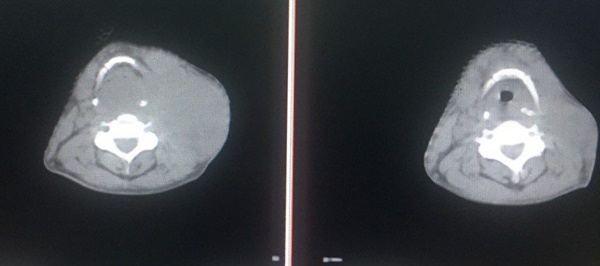

Hình ảnh chụp CT cho thấy tổn thương đáp ứng rất tốt với phác đồ điều trị (Ảnh trái: Trước điều trị và ảnh phải: Sau điều trị)

Tháng 6/2021, người đàn ông này đến Bệnh viện Đa khoa tỉnh Phú Thọ và được chẩn đoán mắc ung thư hạ họng giai đoạn 3, ung thư thực quản giai đoạn 2 chưa di căn xa. Ông được áp dụng phác đồ điều trị hóa trị và xạ trị đồng thời, có chỉ định mở khí quản, thở qua canyul (do khối u chèn ép gây khó thở). Sau một tháng, ông nuốt được, không còn khó thở, hạch cổ và u nhỏ đi nhiều. Hiện tại, bệnh nhân vẫn được điều trị để hoàn thành phác đồ.